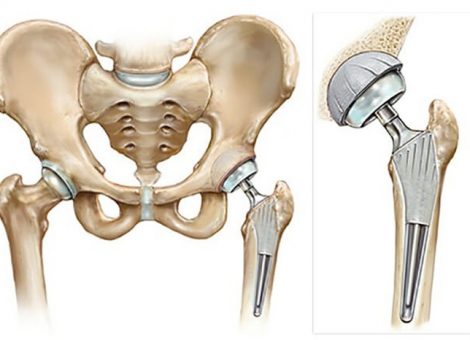

پروتز کامل لگن ، تعویض مفصل آسیب دیده با مفصل مصنوعی در بیمارانی است که مفصل لگن به شدت آسیب دیده است. پروتز لگن شامل قسمت های اصلی ساخته شده از کبالت کروم یا تیتانیوم و متشکل از اتصالات پلاستیکی ، فلزی یا سرامیکی است که در آنجا به آنها می پیوندند.

پروتز لگن به دو طریق می تواند به استخوان وصل شود. در بیماران مسن که کیفیت استخوان آنها خوب نیست ، پروتز با فیلری بنام سیمان استخوان بر روی استخوان ثابت می شود. به این نوع پروتز، پروتز لگن سیمانی گفته می شود. در بیماران جوان تر که از کیفیت استخوانی خوبی دارند ، پروتزهای پوشانده شده با ماده متخلخل بسیار محکم در استخوان قرار داده می شوند و سپس استخوان بدن از طریق منافذ روی پروتز ثابت می شوند. به این نوع پروتز، پروتز بدون سیمان گفته می شود.

پروتز لگن